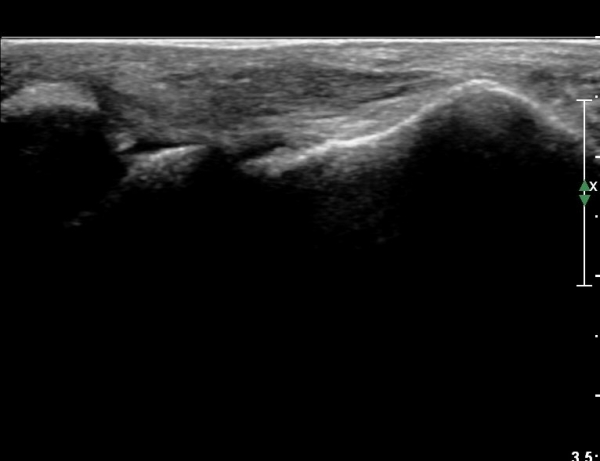

Àü°ÅºñÀδë Á¾´Ü¸é°Ë»ç¿¡¼­  Àü°ÅºñÀδëÀÇ ÆÄ¿­À» º¸ÀÓ(»çÁø 2).